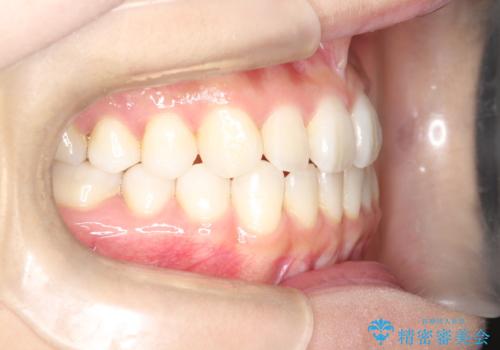

軽度の前歯のガタガタをインビザラインでの目立たない矯正

- 前歯のガタガタを主訴に来院されました。

軽度であったため、枚数制限のあるタイプのインビザラインのプランで治療することとしました。

軽度のガタガタを目立たずに手軽に矯正できるのもマウスピース矯正の魅力といえます。